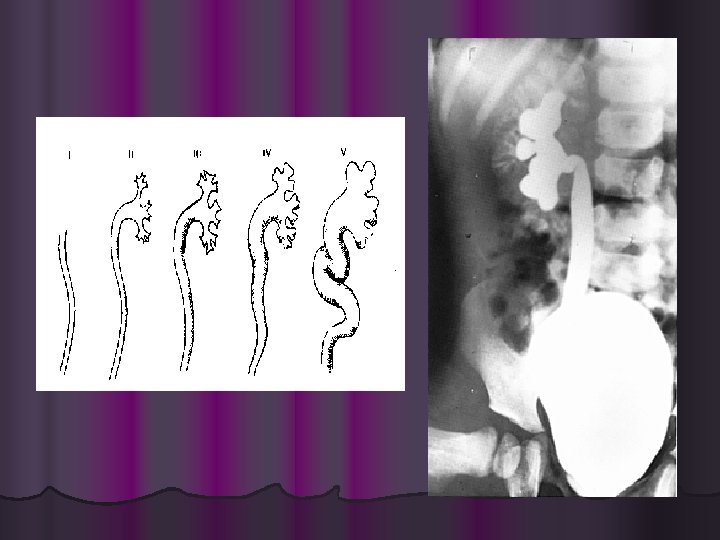

PIELONEFRITIS CRONICA. • • • Episodios frecuentes de PN clinica o subclinica. Bacteriuria asintomatica. Leucocituria y cilindros leucocitarios. Cicatricez en la superficie renal. HAS. Azoemia e Insuficiencia Renal.

INDICACIONES PARA ESTUDIO DE IMAGEN EN PACIENTES CON UTI. l l l l l Niños con UTI. DM. Azoemia. Antecedentes de litiasis urinaria. Sospecha de disfuncion vesical. Hematuria persistente. Cirugia urologica previa. Fiebre y/o dolor prolongado despues de inicio de terapia antibiotica. Infeccion recurrente. MO inusuales o desdobladoras de urea.